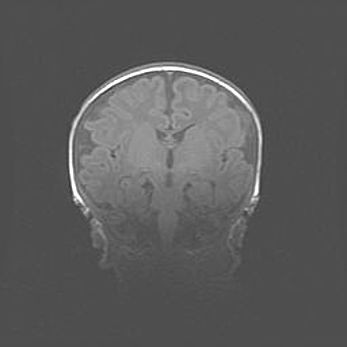

Лейкомаляция с кистозно-глиозной дегенерацией головного мозга.

Возраст: 2 месяца 25 дней

Вес: 6400 г

Окружность головы: 40 см

Срок гестации: 41 неделя

Лейкомаляцию относят к ишемически-гипоксическим повреждениям головного мозга, диагностируемым у новорожденных. При лейкомаляции в головном мозге обнаруживают очаги некроза, возникшие после тяжелой гипоксии и нарушения кровотока. В процессе морфогенеза очаги проходят три стадии: 1) развития некроза, 2) резорбции и 3) формирования глиозного рубца или кисты. Перивентрикулярная лейкомаляция (ПЛ) встречается примерно в 12% случаев среди новорожденных, обычно – у недоношенных детей, причем, частота ее зависит от массы, с которой младенец появился на свет. Наибольшее число малышей страдает лейкомаляцией, если масса при рождении 1500-2500 г.